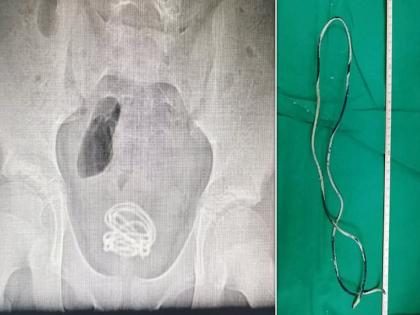

मीडिया रिपोर्टनुसार, हा कारनामा करणाऱ्या १३ वर्षीय मुलाचं नाव Xiao He असं आहे. त्यानेच प्रायव्हेटमध्ये लघवी कुठून येते हे शोधण्यासाठी वायर टाकली. जेव्हा त्याच्या पालकांना दिसलं की, त्याच्या लघवीतून रक्त येतंय तेव्हा त्याला लगेच हॉस्पिटलमध्ये दाखल करण्यात आलं. त्याने वापरलेला हा धातूचा वायर ७० सेंटीमीटर लांब आहे. (दात घासता घासता तरूणीनं चुकून टुथब्रश गिळला; X-ray रिपोर्ट पाहून डॉक्टरांना धक्काच बसला)

डेली मेलने दिलेल्या वृत्तानुसार, हॉस्पिटलने याबाबतची माहिती चायनीज सोशल मीडिया प्लॅटफॉर्मवर शेअर केली आहे. डॉक्टरही या मुलाने केलेला कारनामा पाहून हैराण झाले होते. त्यांना एक्स-रेमध्ये आढळून आलं की, त्याच्या ब्लॅडरमध्ये वायर अडकली आहे. या मुलावर Songshan Lake Central Hospital of Dongguan या हॉस्पिटलमध्ये उपचार केले गेले. (बूटात लपवले १०० पेक्षा जास्त विषारी जिवंत कोळी; कारण वाचून तुम्हीही हादराल....)

अखेर डॉक्टरांनी तासांच्या मेहनतीनंतर cystoscope या उपकरणाने त्याच्या प्रायव्हेट पार्टमधील दोन फूट लांब वायर काढली. Dr Cai Chongyue यांनी सांगितले की, 'मला अजिबात अपेक्षा नव्हती की, इतकी मोठी वायर आत ाकली जाऊ शकते. नशीबाने वायर ब्लॅडरला काहीही इजा झाली नाही.